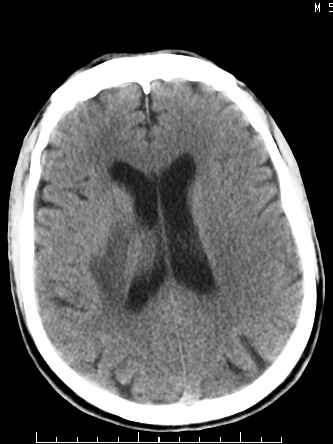

m/50,头昏头痛1月,近3天感觉左半肢体活动不利,自述半年前呈患肺tb,腰穿脑脊液未见特殊改变。现做头颅ct请大家会诊。

ct值?是囊变?梗塞软化灶形成

结核性脑膜炎,结核瘤,梗塞灶三症并存,提示颅内结核感染可能性大。